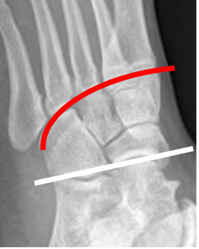

Las articulación tarsometatarsiana (Entre las cuñas/cuboides y los metatarsianos) es conocida como de Lisfranc y la mediocarpiana (Entre el calcáneo/talo y escafoides/cuboides), como de Chopart. (Fig 5).

Fig 5. Articulaciones del mediopié.

Rx oblicua. Articulación de Chopart: Línea blanca y de Lisfranc: Línea roja.